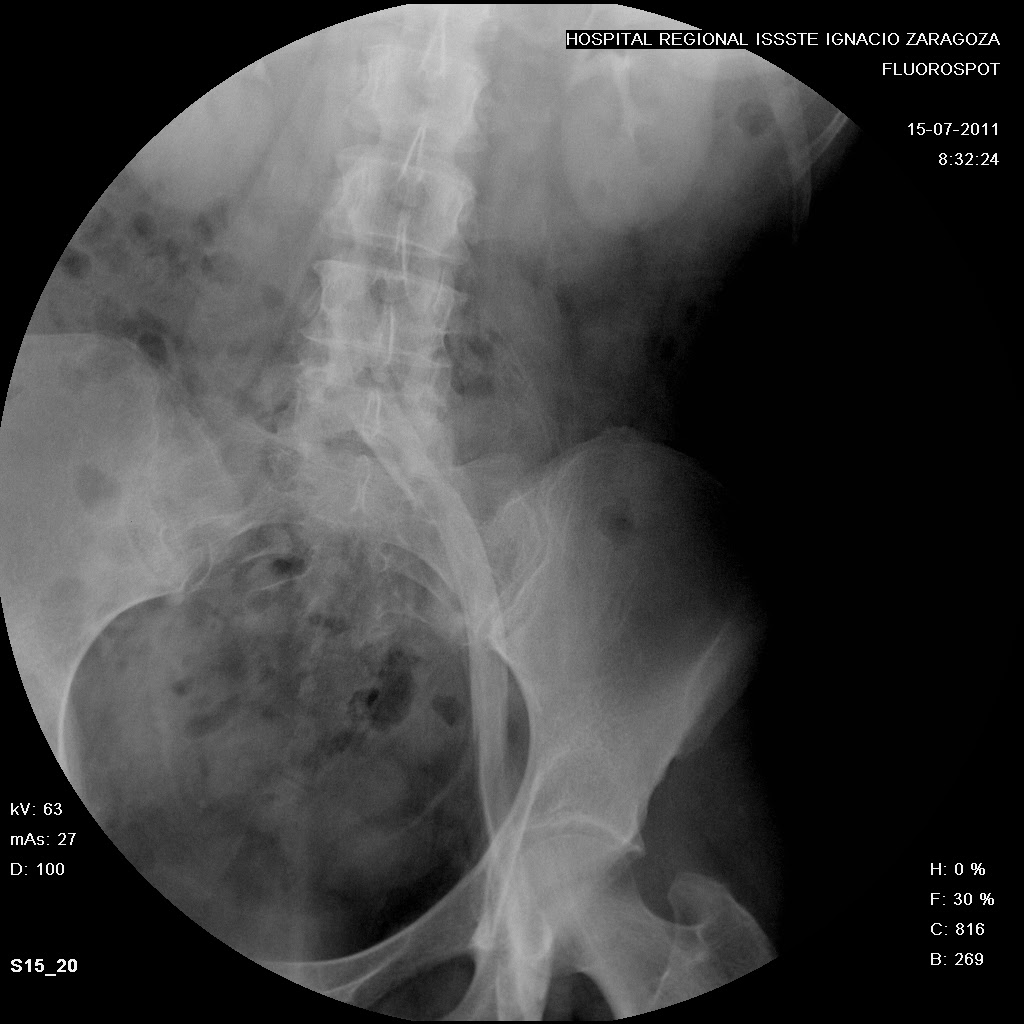

FLEBOGRAFIA (extremidades inferiores)

"FLEBOGRAFIA DE LOS

MIEMBROS INFERIORES"

(TAMBIEN CONOCIDA COMO ASCENDENTE O PELVICO)

La flebografia es un estudio radiologico el cual consiste en la Introducción de un MC hidrosoluble en el “Torrente Venoso” para observar radiologicamente los Transtornos de las Venas y de sus Valvulas.

Mostrando el grado y magnitud del daño, asi como el tiempo de circulacion.del medio de contraste

"PREVIA RADIOGRAFIA DE LA REGION ANATOMICA A EXPLORAR”

žEl MC se inyecta lentamente y bajo control fluoroscopico

žAl observar el llenado de las venas profundas e iniciarse la comunicación a las venas superficiales de las piernas.

žSe despoja de la ligadura el tobillo y se toma la primera placa en proyeccion AP y LATERAL.

ž Para observar las comunicaciones venosas en 2 incidencias diferentes.

žA continuacion se centra la rodilla y se toma Rx de rodilla AP con la ligadura inferior aun colocada y otra sin ella .

žFinalmente se toma una incidencia lateral u oblicua de rodilla

Posteriormente se centra el muslo abarcando la porcion distal y se elimina la ligadura.

Tomando una Rx de muslo y otra en su porcion proximal, tratando de visualizar el nacimiento de la vena iliaca.

žPor ultimo se centra a la altura de la pelvis o cadera, de manera que permita observar la union de las venas femorales con la cava inferior, dando un ligero masaje en pantorrilla y muslo o elevando manualmente las piernas del pte y tomando AP de pelvis al obsevar la llegada del MC ala vena cava.